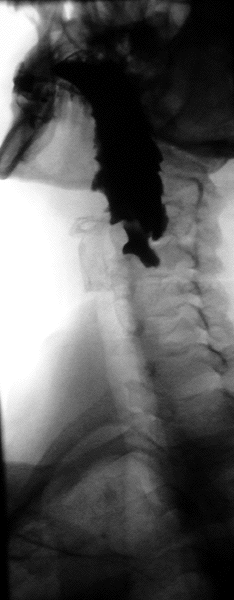

Barium swallow

A barium swallow study is also known as a barium esophagram and needs little if any preparations for the study of the larynx, pharynx, and esophagus when studied alone.[11][12]

Amongst the uses of barium swallow are: persistent dysphagia and odynophagia despite negative esophagogastroduodenoscopy (OGDS) findings, failed OGDS, esophageal motility disorder, globus pharyngeus, assessment of tracheoesophageal fistula, and timed barium swallow to monitor the progress of esophageal achalasia therapy.[13] Barium sulfate suspension such as 100 ml or more of E-Z HD 200 to 250% concentration and Baritop 100% can be used. Water-soluble contrast agent such as Gastrografin (diatrizoate) and Conray (Iotalamic acid) is used instead of barium if oesophageal perforation is suspected. Low osmolar contrast medium with concentration of 300 mg/ml is used instead of gastrografin if there is risk of aspiration or there is tracheoesophageal fistula.[13]

A thick barium mixture is swallowed in supine position and fluoroscopic images of the swallowing process are made. Then several swallows of a thin barium mixture are taken and the passage is recorded by fluoroscopy and standard radiographs. The procedure is repeated several times with the examination table tilted at various angles. A total of 350–450 mL of barium is swallowed during the process.[14][15] Normally, 90% of ingested fluid should have passed into the stomach after 15 seconds.[16]

Right anterior oblique (RAO) view is to see the oesophagus clearly, away from overlapping spine.[13] AP (anterior-posterior) view is also done to visualise the gastroesophageal junction.[13] AP and lateral views are also done to visualise the hypopharynx during swallowing at a frame rate of 3–4 per second. Left posterior oblique (LPO) position is used to identify hernias, mucosal rings, and varices.[13]